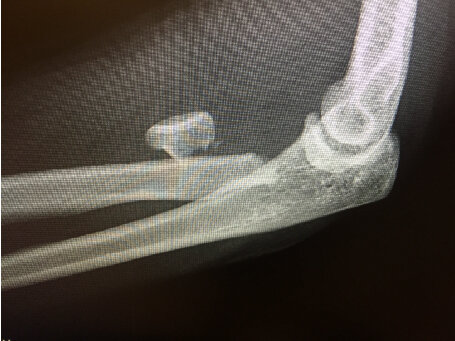

This is an unusual case of an elbow fracture/dislocation with an extruded radial head and an intact proximal ulna.

48 YO RHDF with Elbow Dislocation and Anteromedially Extruded Radial Head

The patient fell off her porch onto her extended left arm, sustaining the injury shown below. She reports immediately seeing her elbow “crooked” and states that she grabbed her forearm with her dominant hand, jerked, and felt her elbow pop back into place. Below are her left elbow and wrist X-rays and CT from the ER, where she was placed in a splint. No reduction was performed in the ER. She presented to my office 2 days later. Neurovascular exam was normal.